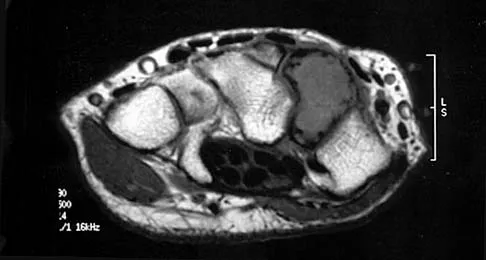

Question 40

An infant is born with a mass that involves both the volar and dorsal compartments of the left arm. A clinical photograph and biopsy specimen are shown in Figures 41a and 41b. What is the best initial course of action?

Explanation